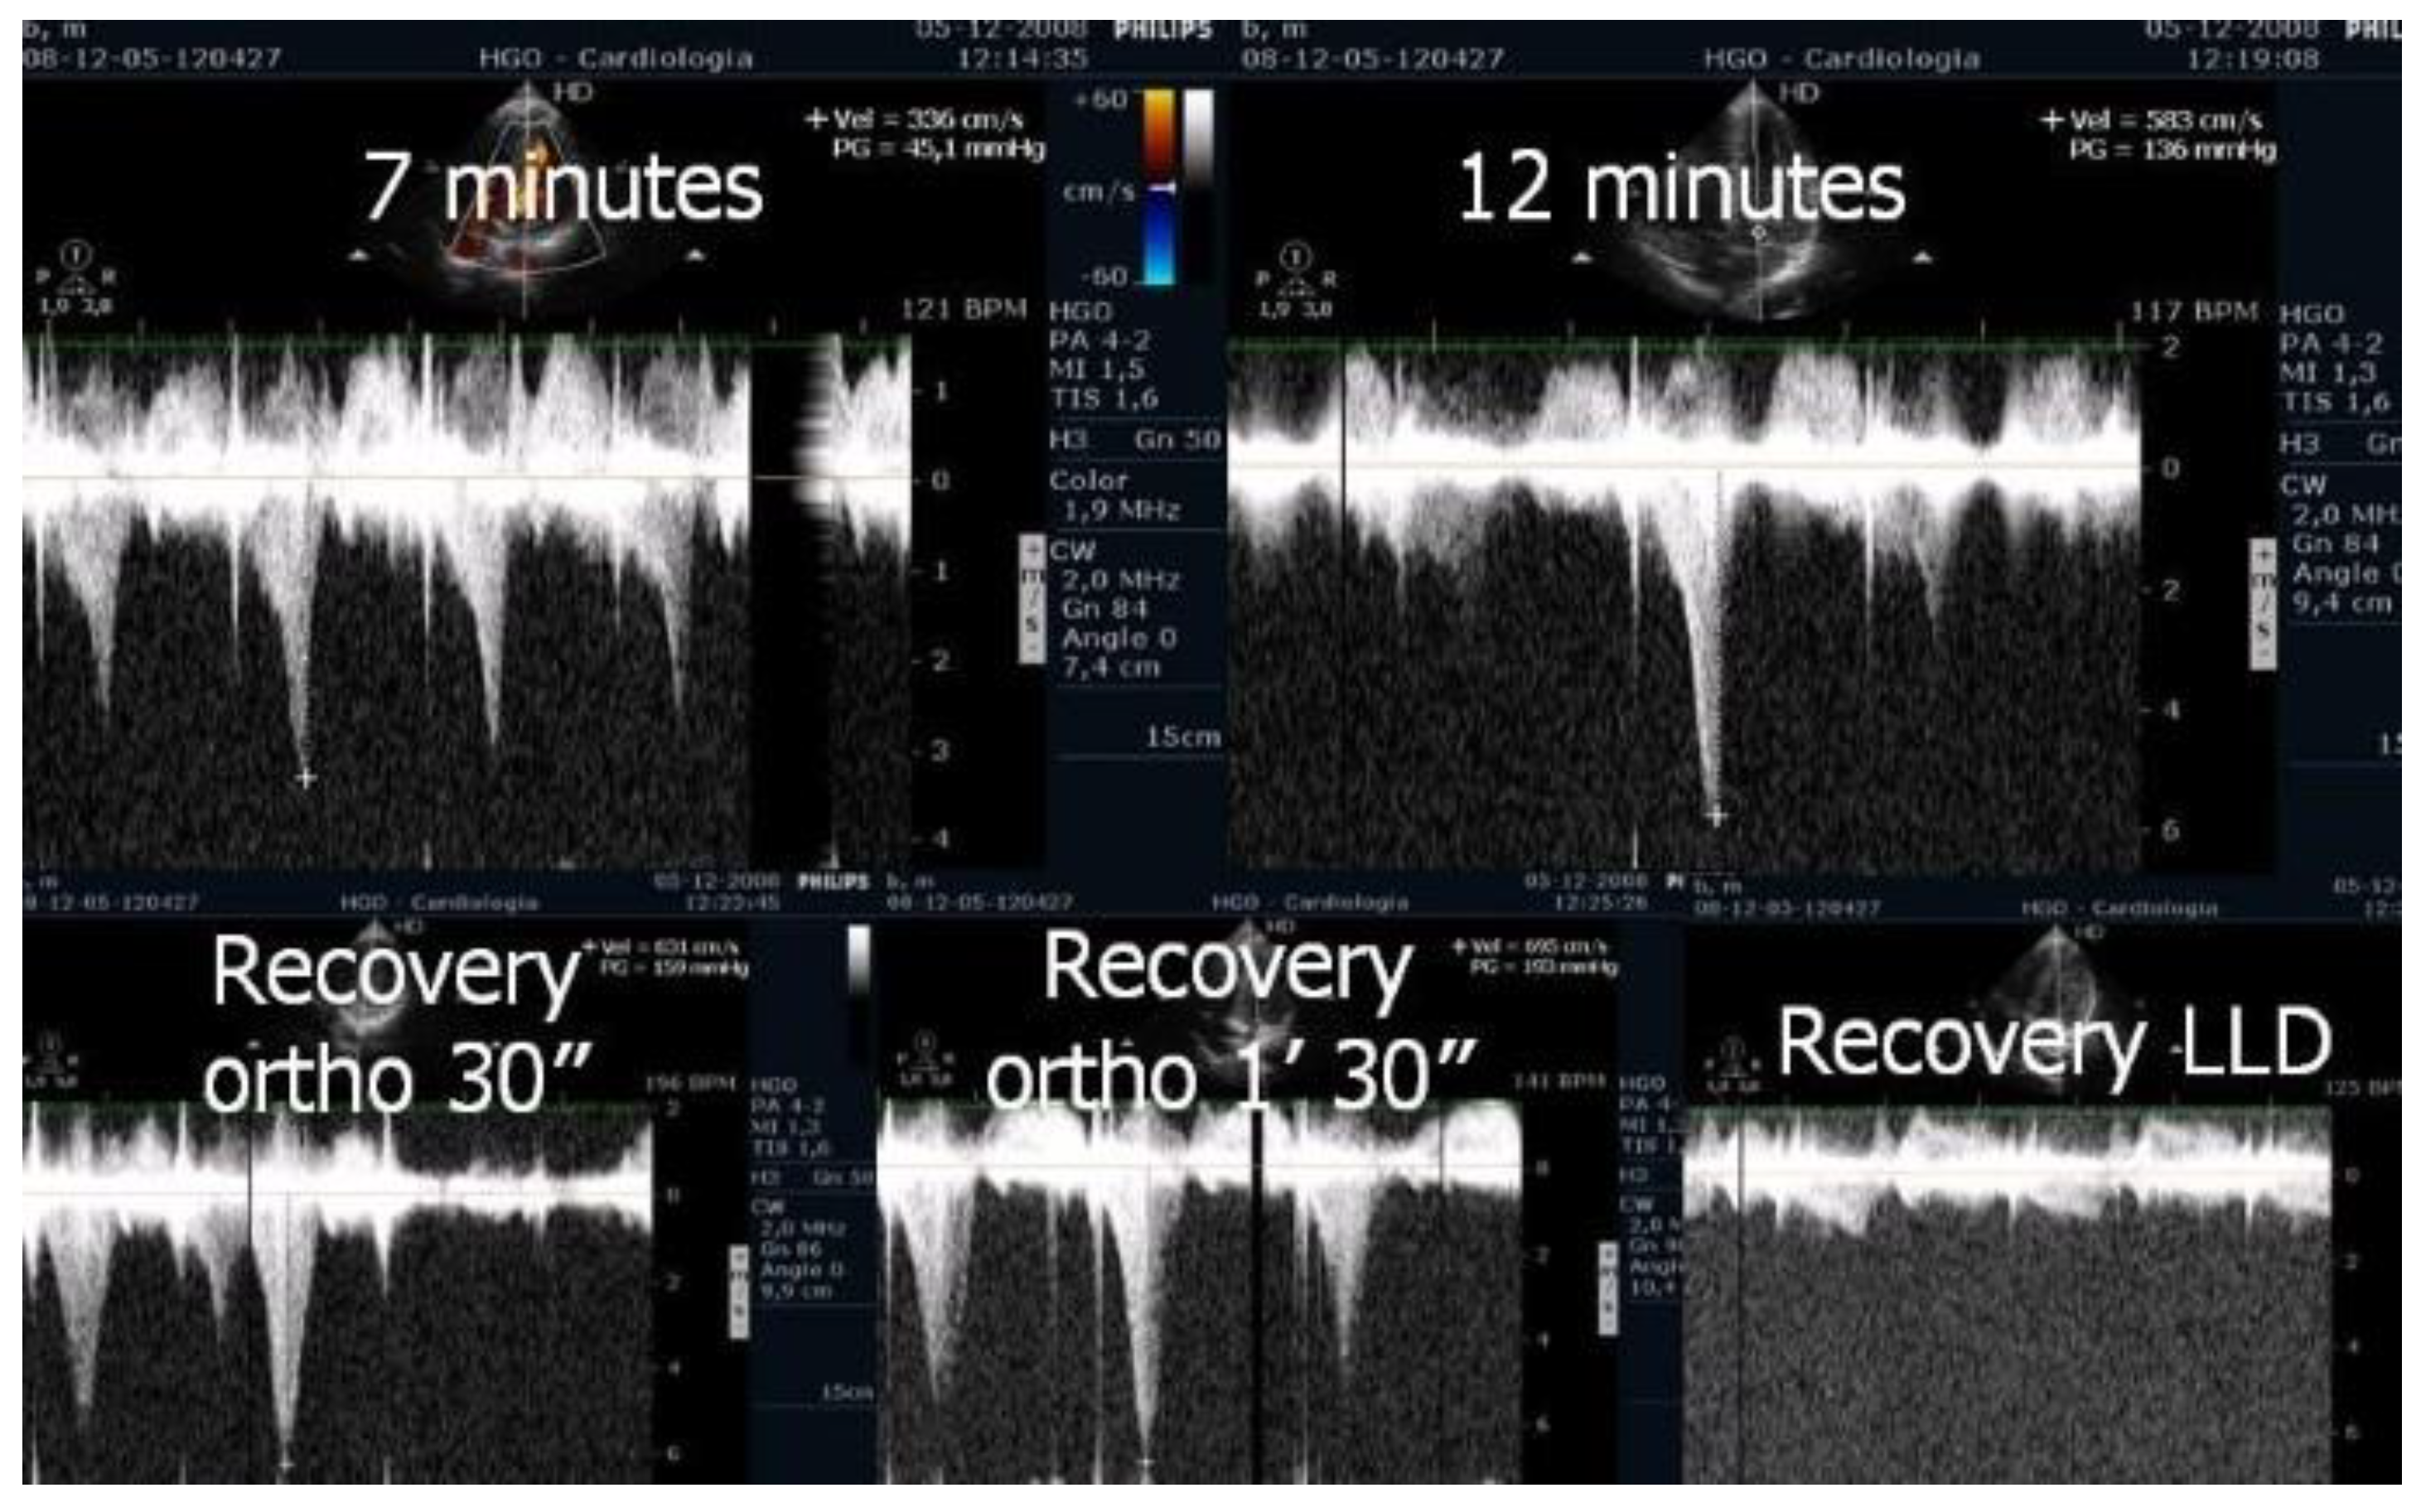

| in [1] | Evaluate IVGs with echocardiography during treadmill exercise and post-exercise in the upright position in patients with HCM. | 17 HCM | Research | Three patients with non-obstructive HCM at rest developed IVGs during exercise. One patient developed this gradient only during orthostatic recovery. The mean IVG in left lateral decubitus (LLD) was 49 ± 4 mm Hg; in orthostatic position it was 62 ± 29 mm Hg (p < 0.001 versus in LLD); at peak exercise it was 83 ± 35 mm Hg (p < 0.001 versus supine rest); during recovery it was 96 ± 35 mm Hg (p < 0.001 versus peak exercise) |

| [40] | The relation between functional capacity and exercise-induced LVOT obstruction in HCM is incompletely defined. The time course of the provoked gradients and the relation to exercise performance were assessed. | 74 HCM | Research | In patients with non-obstructive HCM at rest, the earlier onset of LVOT gradients during treadmill exercise was associated with impaired exercise performance. These findings have yielded insights into the determinants of functional impairment in HCM and support the potential value of exercise echocardiography in the clinical evaluation of patients with HCM. |